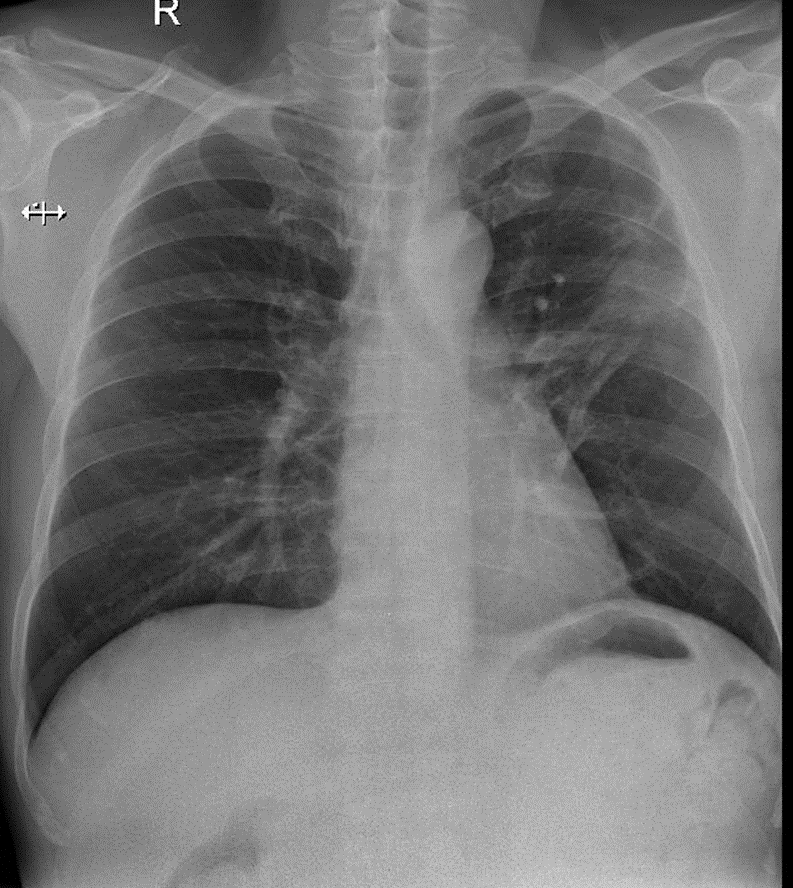

Hãy phân tích tình huống Nam

1-Xơ thùy trên phổi (T)